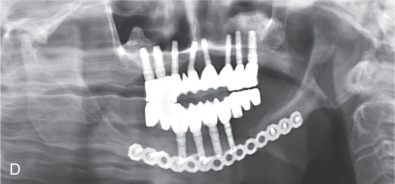

All of these systems allowed for convalescent function – life without MMF. RIF had the potential of dramatically shortening the course of treatment. However, its use was highly technique-sensitive with a steep learning curve. Thus, the incidence of complications increased dramatically due to operator error. Complications related to inadequate reduction – “the OIF” (open internal fixation … without the reduction) ( Figs. 1.16.1–1.16.3 ), inadequate fixation ( Figs. 1.16.4–1.16.7 ) and surgical misadventure ( Fig. 1.16.8 ) began to appear. Indeed, by the early 1990s operator error was the number one cause of mandibular fracture complications. Quite obviously, RIF is very unforgiving. When done poorly, one has a rigidly fixed mistake. The latest series of misadventures are related to the use of IMF screws. Bone-anchored arch bars will most likely be next. Not all believe that RIF and convalescent function is cost-effective with respect to the increased cost, potential for complications, and patient acceptance.